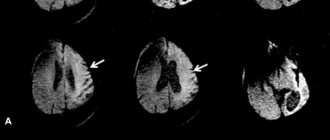

PPP is characterized by the occurrence of seizures in one of the upper limbs or in the face. These seizures lead to deviation of the head and aversion of the eyes towards the hemisphere contralateral to the localization of the epileptic focus. Focal seizures may begin in a limited area or become generalized, resembling secondary generalized tonic-clonic seizures. Todd's paralysis (or paresis), expressed in transient weakness for several minutes to several hours, as well as abduction of the eyeballs towards the affected hemisphere, indicate an epileptogenic focus. These phenomena appear in the patient after PPP (postictal period) [1, 4].

Partial seizures with secondary generalization (PSG). Secondary generalized partial seizures are tonic, clonic, or tonic-clonic. PPVH always occurs with loss of consciousness. They can occur in children and adolescents after both simple and complex partial seizures. Patients may have an epileptic aura (about 75% of cases) preceding PPVH. The aura usually has an individual character and can be stereotypical, and depending on the damage to a particular area of ​​the brain, it can be motor, sensory, autonomic, mental or speech [1, 4].

During PPVG, patients lose consciousness; they fall if they are not in a lying position. A fall is usually accompanied by a specific loud cry, which is explained by spasm of the glottis and convulsive contraction of the chest muscles [1].